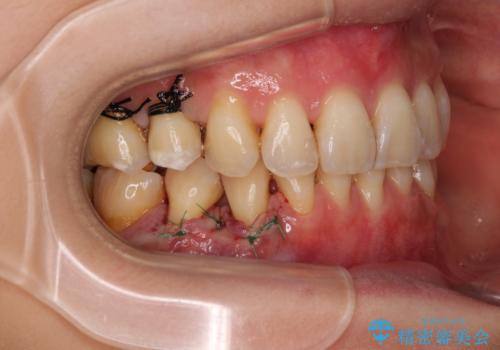

口蓋(上顎の内側)から採取した結合組織(歯肉の内側の組織)を移植することによる、根面被覆術を行うこととしました。

移植片には、極力角化歯肉が多く残るようにし、被覆するだけでなく、歯肉の厚みを増やし、角化歯肉を回復させることができました。